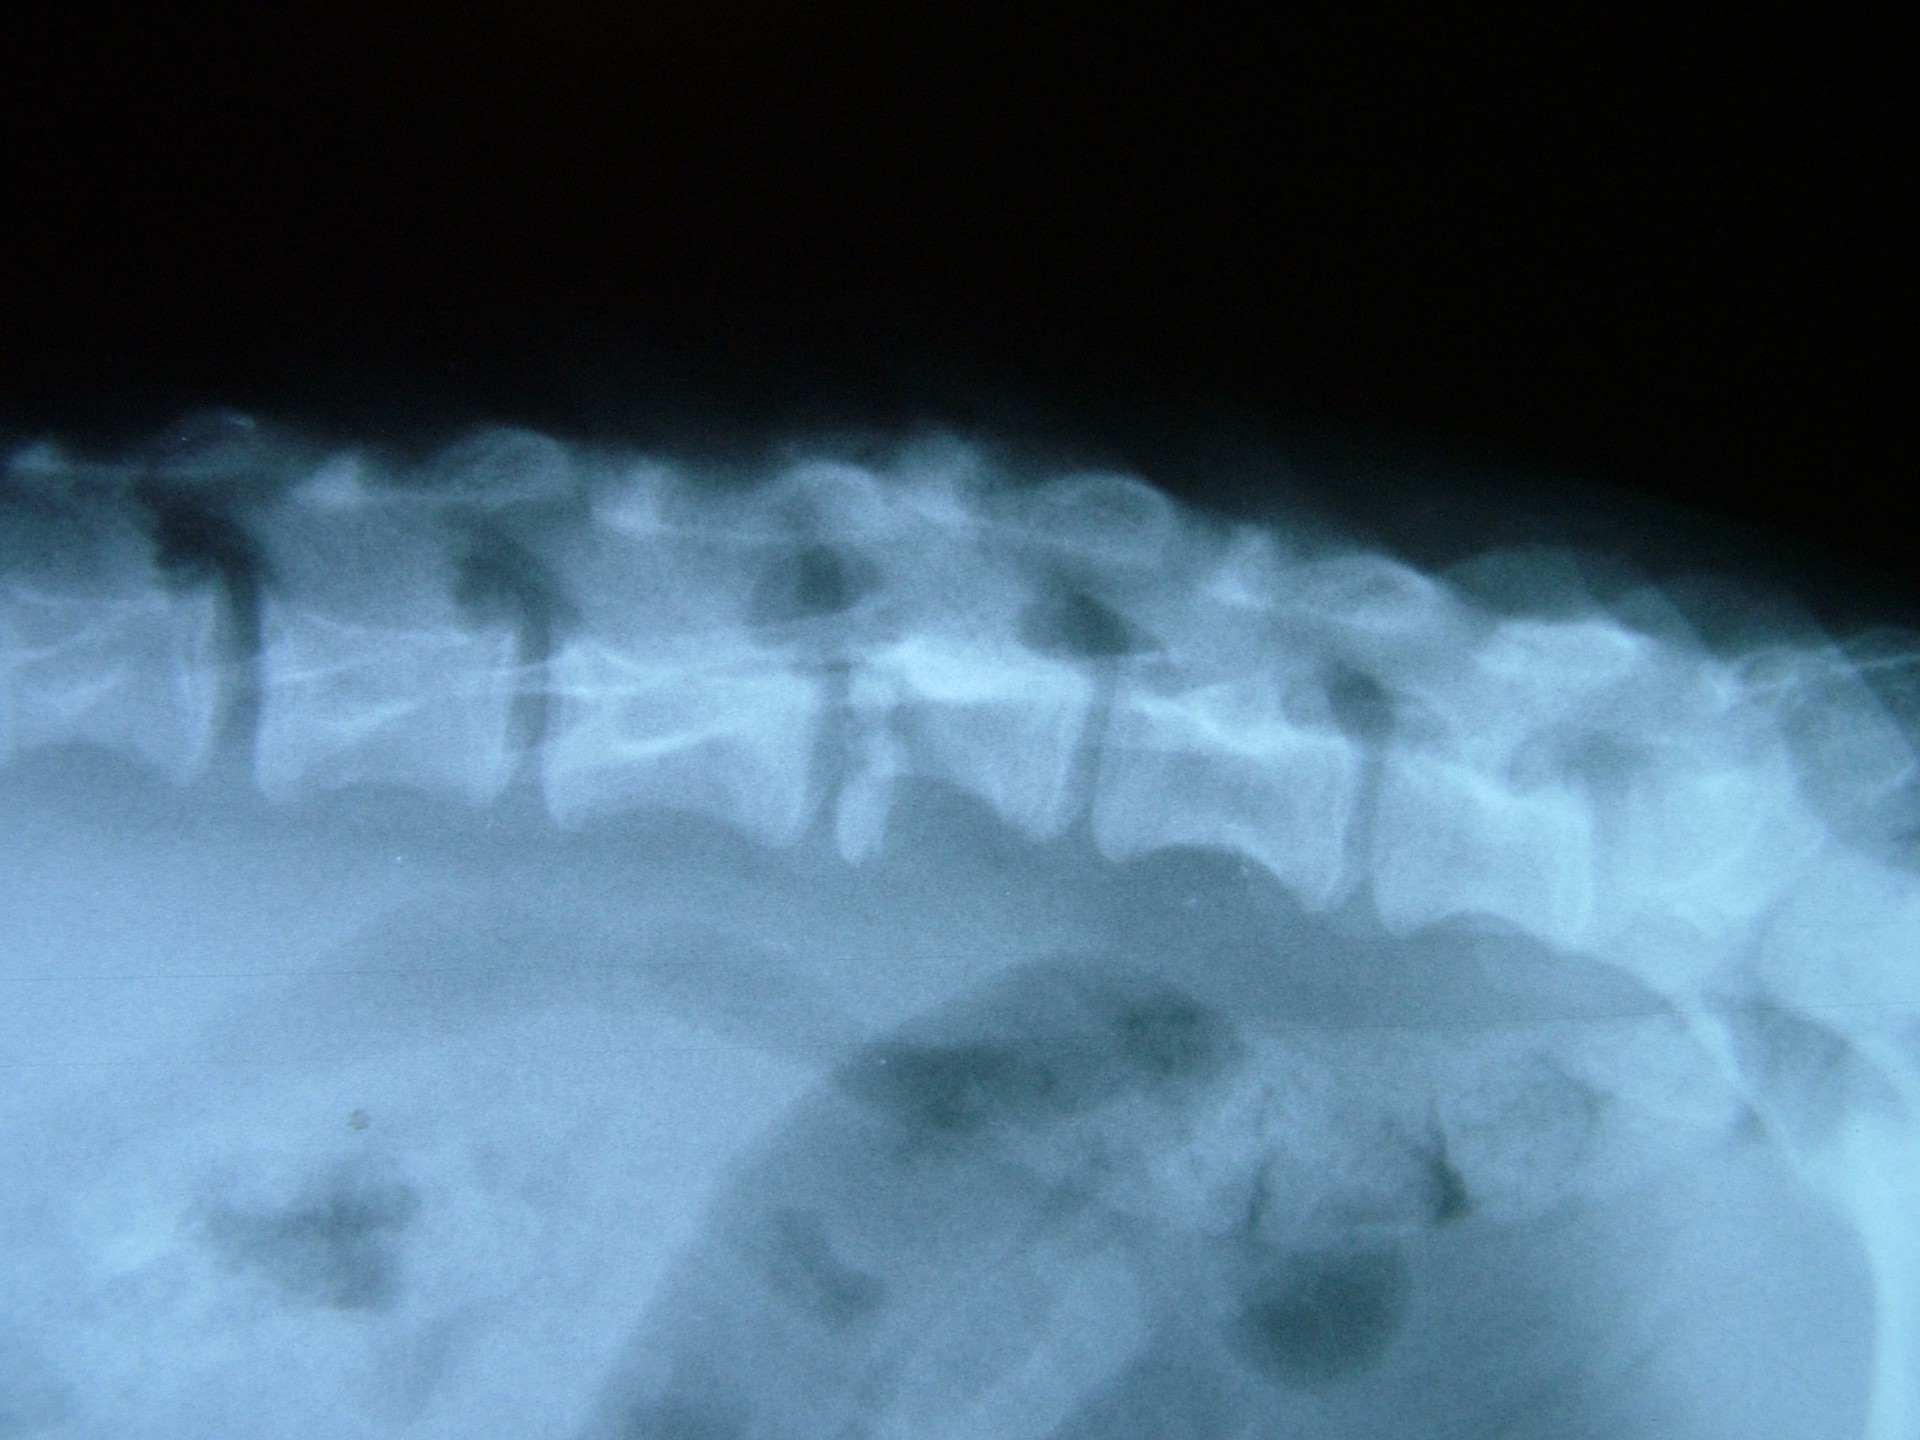

A gerinctörés diagnózisának felállítása komoly döntés elé állítja a tulajdonost és az állatorvost egyaránt. A gerinctörés következtében a gerincvelő minden esetben enyhébb-súlyosabb mértékben sérül. A gerincvelő sérülésének mértékét neurológiai vizsgálattal állapítjuk meg, de a diagnózis felállításához nélkülözhetetlen röntgen felvételről is már információt nyerhetünk a gerincvelő várható állapotáról. A tört végek egymáshoz képest történő kis mértékű elmozdulása esetén a gerincvelő körüli területek bevérzése miatt kialakult neurológiai tünetekkel találkozunk míg nagymértékű elmozdulásuk a gerincvelőt gyakorlatilag olló szerűen elnyírhatja. Így a natív röntgen felvételen a gerinccsatorna elmozdulásából már következtetést vonhatunk le a gerincvelőt ért sérülés mértékéről. A gerincvelő tényleges állapotáról azonban csak neurológiai vizsgálattal győződhetünk meg!

A gerinctörések műtéti ellátása kettős feladatot jelent: egyrészről a törés és elmozdulás következtében kialakult gerincvelő összenyomatást kell megszüntetni, másrészről a tört végeket kell adaptálni és eredeti állapotban - a további elmozdulás megakadályozása érdekében - rögzíteni. A műtéti ellátás során ezért minden esetben az érintett területen a gerinccsatorna felső csontos ívét eltávolítjuk (total laminectomia) így a gerincvelő sérülésének mértéke egyértelműen látható ill. a későbbi összenyomatása elkerülhető.

A törött csigolyatestek adaptációja és rögzítése a nyitott gerinccsatorna mellett komoly kihívást jelent. A későbbi elmozdulás elkerülésére többféle műtéttechnika alkalmazható, melyek közül a csigolyatestek lemezes osteosynthesise ill a fixateur interna használata terjedt el leginkább. Első esetben a sérülés előtti és mögötti csigolyákat lemez és csavarok segítségével egymáshoz rögzítjük, míg az utóbbi esetben a törés előtti és mögötti egy vagy több csigolyatestet két oldalról behelyezett csavarok és egy steril kétkomponensű akrilát műgyanta segítségével rögzítjük.